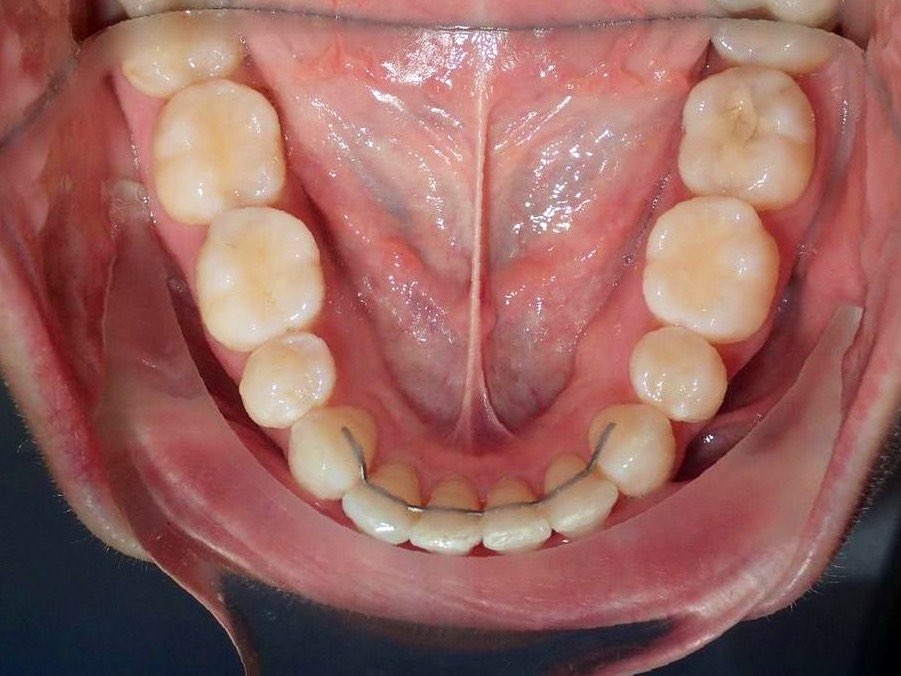

До / После

Лечение Invisalign в течение 1 года с эстетическими штрихами